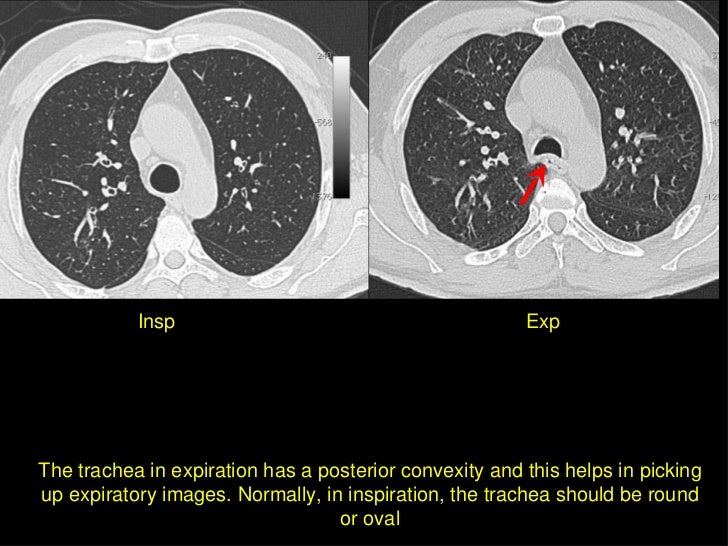

BASICS OF CHEST X RAY PART3 INSPIRATION VS EXPIRATION QUALITY OF X RAY

HRCT In Diffuse Lung Diseases I Techniques And Quality

Approach To Chest X Ray And Interpretation